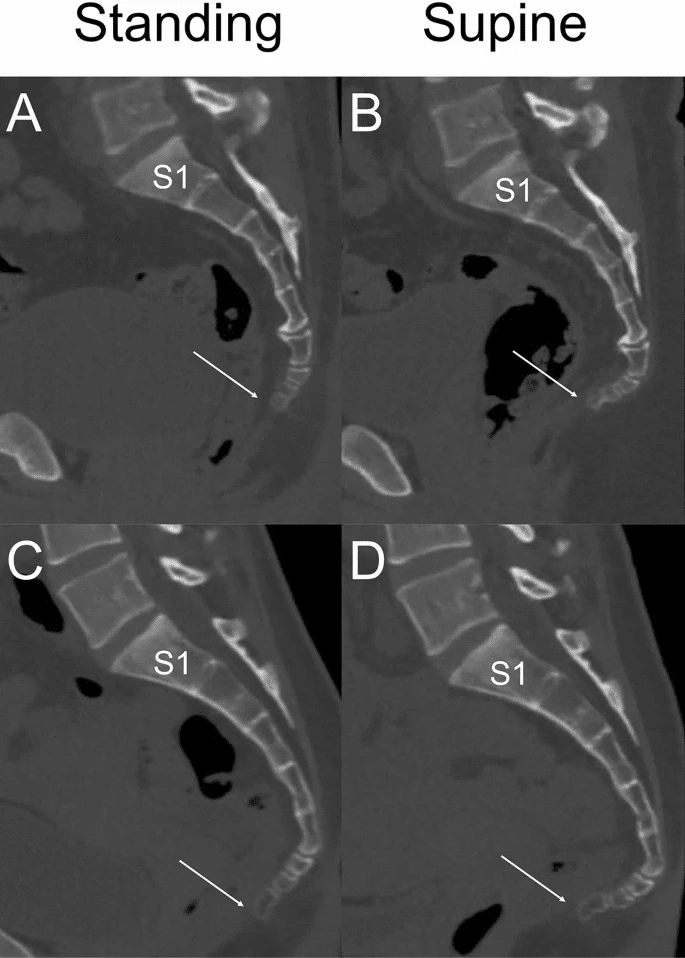

正常アライメント:仙尾骨角(立位/仰臥位、115.0 ± 10.6 mm/105.0 ± 12.5 mm)。尾骨の可動域は前後5〜20度とされます。

体位による変化:座位で体重がかかると尾骨は前屈し、立位では仙骨との角度が変化します。CT研究では、立位と仰臥位で仙尾骨角に有意な差があることが報告されています。

こちらの画像では仙尾関節の動きよりも尾椎間での運動量が大きいですね。